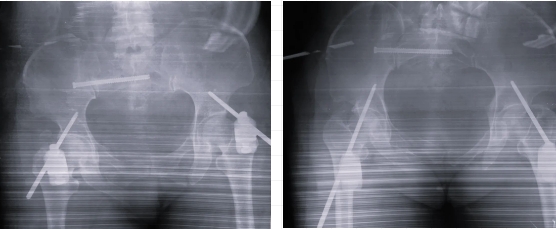

术后X线显示骨折获得满意复位